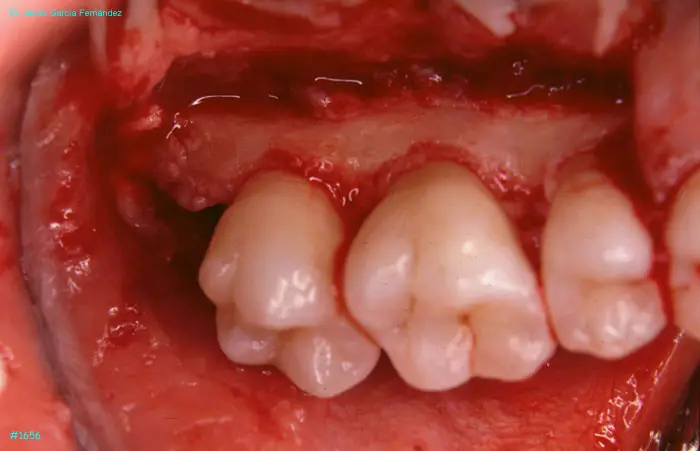

Atlas of Surgical Techniques in Periodontics. Chapter IV. Atlas de Técnicas Quirúrgica en Periodoncia

image 169